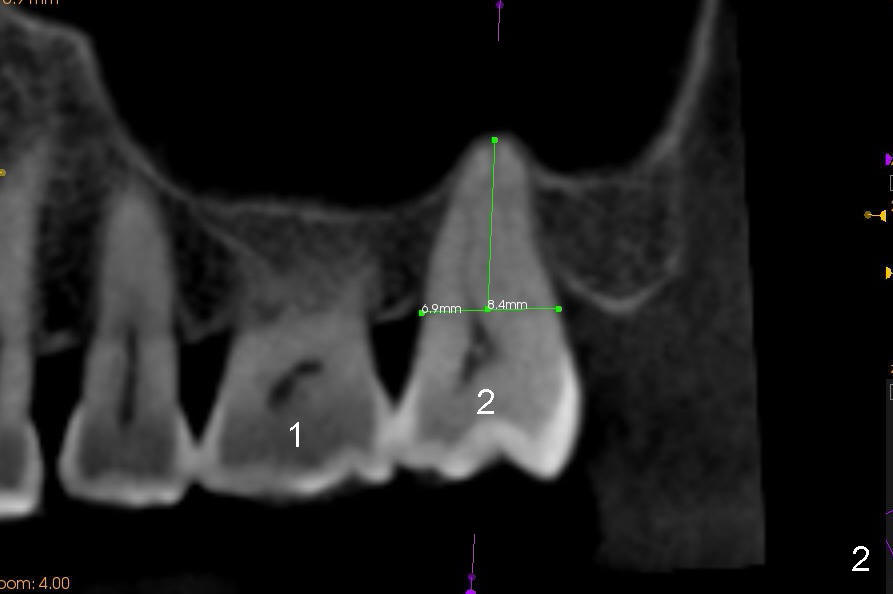

The upper 2nd molar have 3 roots with limited furcation. The buccal ones may be fused (Fig.1 (CT coronal section),2 (sagittal)). After extraction, there are 2 sockets (Fig.1'). When 3 roots are fused, there is a single large socket.

When the buccal roots are fused, there are 3 potential sites for immediate implant (Fig.1'): septum (*), buccal (B) and palatal (P) sockets. Septal placement (6.9x8 mm bone level implant) is the most ideal for restoration (Fig.3). The length of the implant can be increased (10 mm) with sinus lift so that the base of the implant between the buccal and palatal apices in height (Fig.4). Primary stability is derived mainly from the implant body engagement into the septum (Fig.5 coronal section through the septum). If bone density in the septum is high, a small implant may be appropriate (Fig.6,7: 6.4x8 mm). The large implant (6.9 mm) is chosen so that amount of bone graft to be used (Fig.8 red circles) is less.